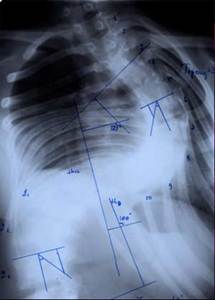

До сих пор в ортопедии принято множество методик измерения угла искривления позвоночника, и, соответственно, множество различных классификаций с разными величинами углов в градусах. Измеряется искривление так: на рентгенограмме надо провести несколько прямых линий между позвонками, а затем измерить углы между ними. В нашей стране наиболее распространена классификация, предложенная В.Д. Чаклиным. В иностранных научных источниках чаще приводится метод Дж. Кобба. Суть его заключается в следующем: на рентгеновском снимке позвоночника врач измеряет S-образное двойное искривление. В верхнем участке искривления с помощью линейки проводят две горизонтальные линии: одна над верхним позвонком, от которого идет кривизна, другая - над нижним. Если провести еще две линии, идущие перпендикулярно первым, образуется угол. Его и измеряют в градусах

Классификация выраженности сколиоза по В.Д. Чаклину (слева), по Лж. Коббу (справа) Степени тяжести сколиоза (углы искривления позвоночника, в градусах) Графический расчет на рентгенограмме: а - I степень; б - II степень; в - III степень; г - IV степень.

По В.Д. Чаклину

По Дж. Коббу

I степень 180 - 175 меньше 15

II степень 175-155 20-40

III степень 155-100 40-60

IV степень меньше 100 больше 60